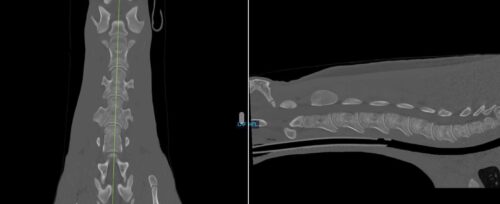

Nova, an 8-day old Quarter Horse filly, presented to Animal Imaging following a 2-day history of right sided head tilt with no known evidence of trauma. She was worked up by a boarded internal medicine specialist who found no significant abnormalities on physical examination, bloodwork, and initial radiographic findings. The filly presented for head and neck computed tomography (CT) to look for a possible cause of the head tilt and initial scan findings were relatively unremarkable aside from the appearance of debris seen within the right middle ear (blue arrow). Due to the lack of significant findings and the owner’s goals of identifying any significant performance limiting abnormalities within the foal, she was then taken to magnetic resonance imaging (MRI) for same day brain imaging. The collected images are shown below:

These images show a CT of the neck of a horse. The image on the left is a bird’s eye view of the vertebrae of the neck and the image on the right shows an image taken from the side of the horse’s neck.